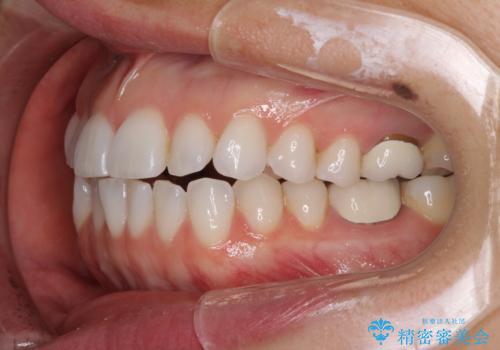

ちょっとしたデコボコをしっかりと改善したい インビザライン矯正

- 前歯のデコボコと上下スペースと前歯の隙間を気にして来院された患者様です。

目立たない装置を希望とのことでインビザラインにより、デコボコを解消しつつ、上下の前歯の隙間を閉じていくこととしました。

デコボコはあっという間に解消されましたが、上下前歯の隙間がなかなか解消されませんでした。

飲み込みの際に舌を前方に突出する癖があり、飲み込みの度に前歯に強く接触していたため、上下前歯の隙間が維持されていました。

舌の訓練を徹底していただいたことで、徐々に隙間は解消され、きれいな歯列に整えることができました。